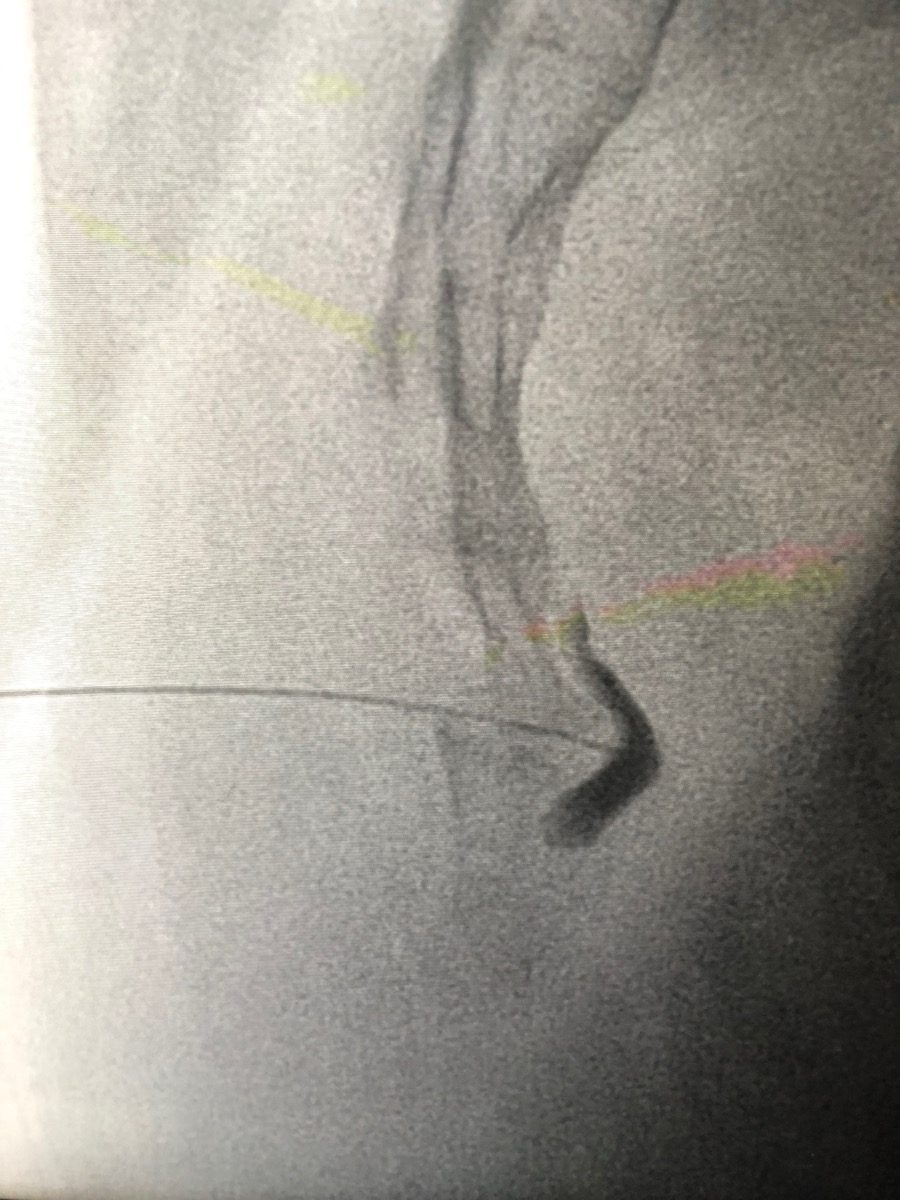

How is a Ganglion Impar Block or RFA performed?

You lie face-down on the procedure table. The skin over the lower back is cleaned and numbed. Under live X-ray guidance, a thin needle is guided to the sacrococcygeal junction, the junction between the sacrum and tailbone. Contrast dye confirms the needle tip is in front of the coccyx, near the ganglion impar. The anaesthetic or RFA current is then applied. The whole process takes about 45 to 60 minutes.